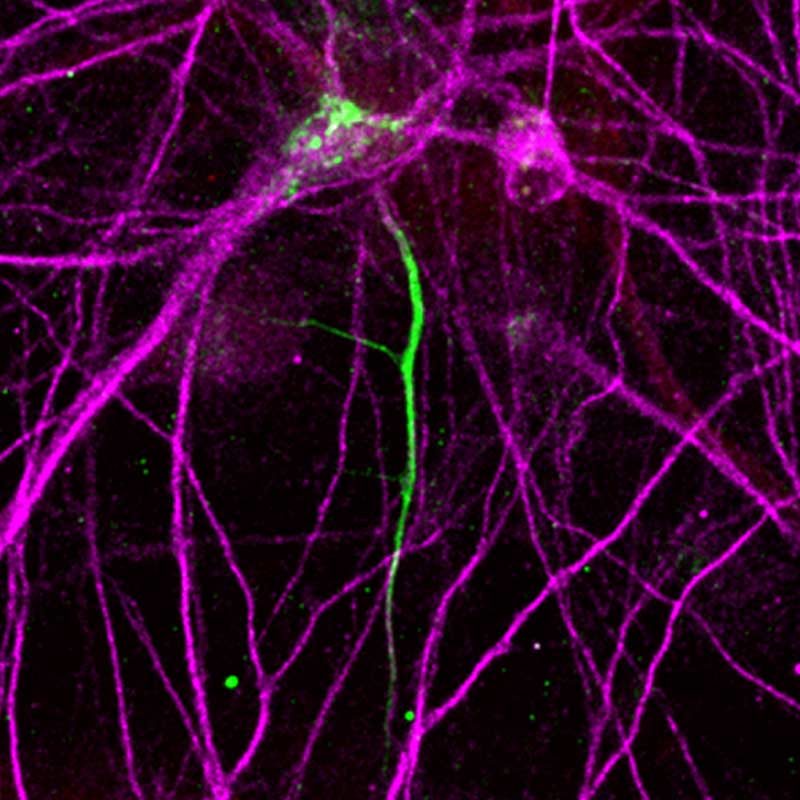

Two copies of SCN2A

Nerve cells (pink) with two functioning copies of the SCN2A gene easily connect with other nerve cells and produce normal-sized, short wires (green).